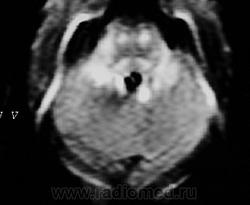

ГМ. Рассеянный склероз 2. +

Рассеянный склероз